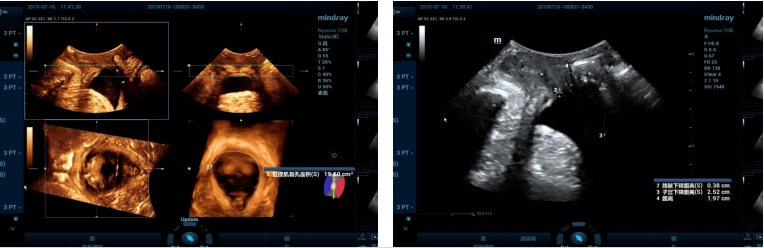

(二)三维盆底彩超检查

盆腔器官脱垂主要是由于分娩损伤,长期慢性咳嗽、便秘、下蹲时间过长至腹压增高等因素导致。特别是绝经后女性雌激素水平减低、盆底组织萎缩退化而薄弱,可导致盆底肌肉松弛。通过三维盆底超声技术可以直观显示女性盆腔器官有无脱垂以及观察盆底结构、肛提肌裂孔形态和大小的变化,以获取诊断信息,制定治疗方案。

阿坝州人民医院超声科引进了两台四维彩色多普勒超声诊断仪,目前已有近300名女性患者做了盆底三维彩超检查,阳性率达70%以上。